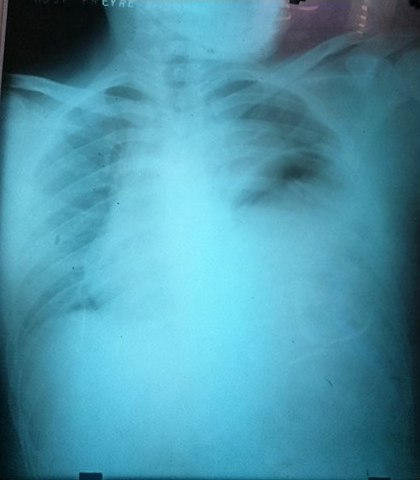

Una nueva radiografía de tórax AP, informó de la presencia de cámara gástrica en el interior del hemitórax izquierdo, elevación del hemidiafragma izquierdo y desplazamiento de la silueta cardiaca. (Figura 3).